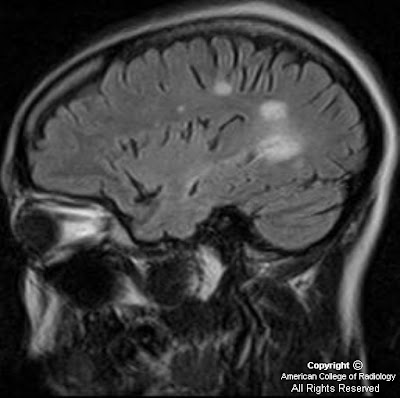

34 yo) Figure 1: Sagittal FLAIR image delineates septo-callosal interface hyperintensities, perpendicular periventricular hyperintensities extending into the deep white matter, and a juxtacortical lesion.

38 yo)Figure 3: Sagittal FLAIR (3a) and axial FLAIR (3b) images demonstrate confluent periventricular and juxtacortical oval plaque-like hyperintense lesions perpendicular to the ventricular axis known as “Dawson’s fingers”.